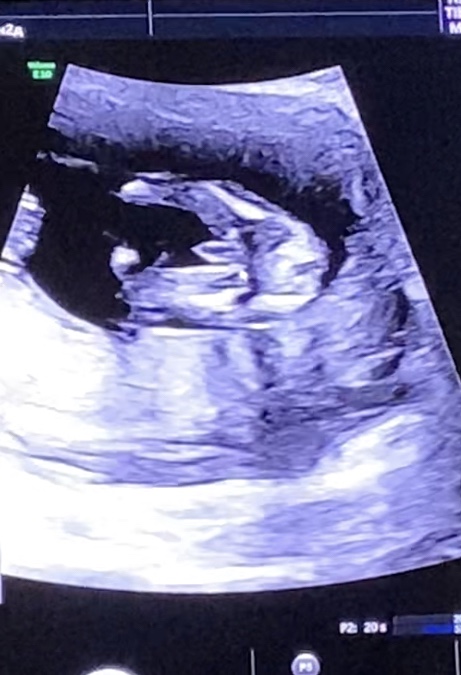

Сегодня на узи подтвердили мальчика 🥰 с анализом совпало ❤️ сохранила картинку 😄покажу потом его невесте 😂

@hellochka, девочка ) если приблизить видно между ног как бы кофейное зёрнышко с разрезом

С таким размером то и не поспоришь 🤭